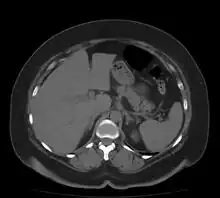

Bowel

.jpg.webp)

Both large and small bowel can be affected by ischemia. Ischemia of the large intestine may result in an inflammatory process known as ischemic colitis. Ischemia of the small bowel is called mesenteric ischemia.